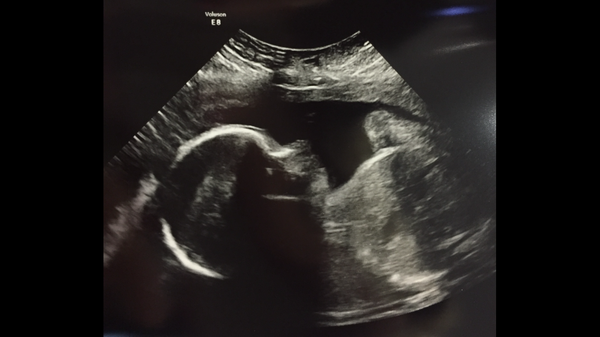

Hi Blondes, thanks, I'm hoping I'll be over the worst of it soon! Sorry you had a rough day too, although it's a lovely scan picture :)

Blondes: yay on the scan, nay on the glucose. You survived and it's done.

Hi to everyone else and hang in there. Blondes that is a gorgeous can picture! Pip1982 how are you doing? Big hug.